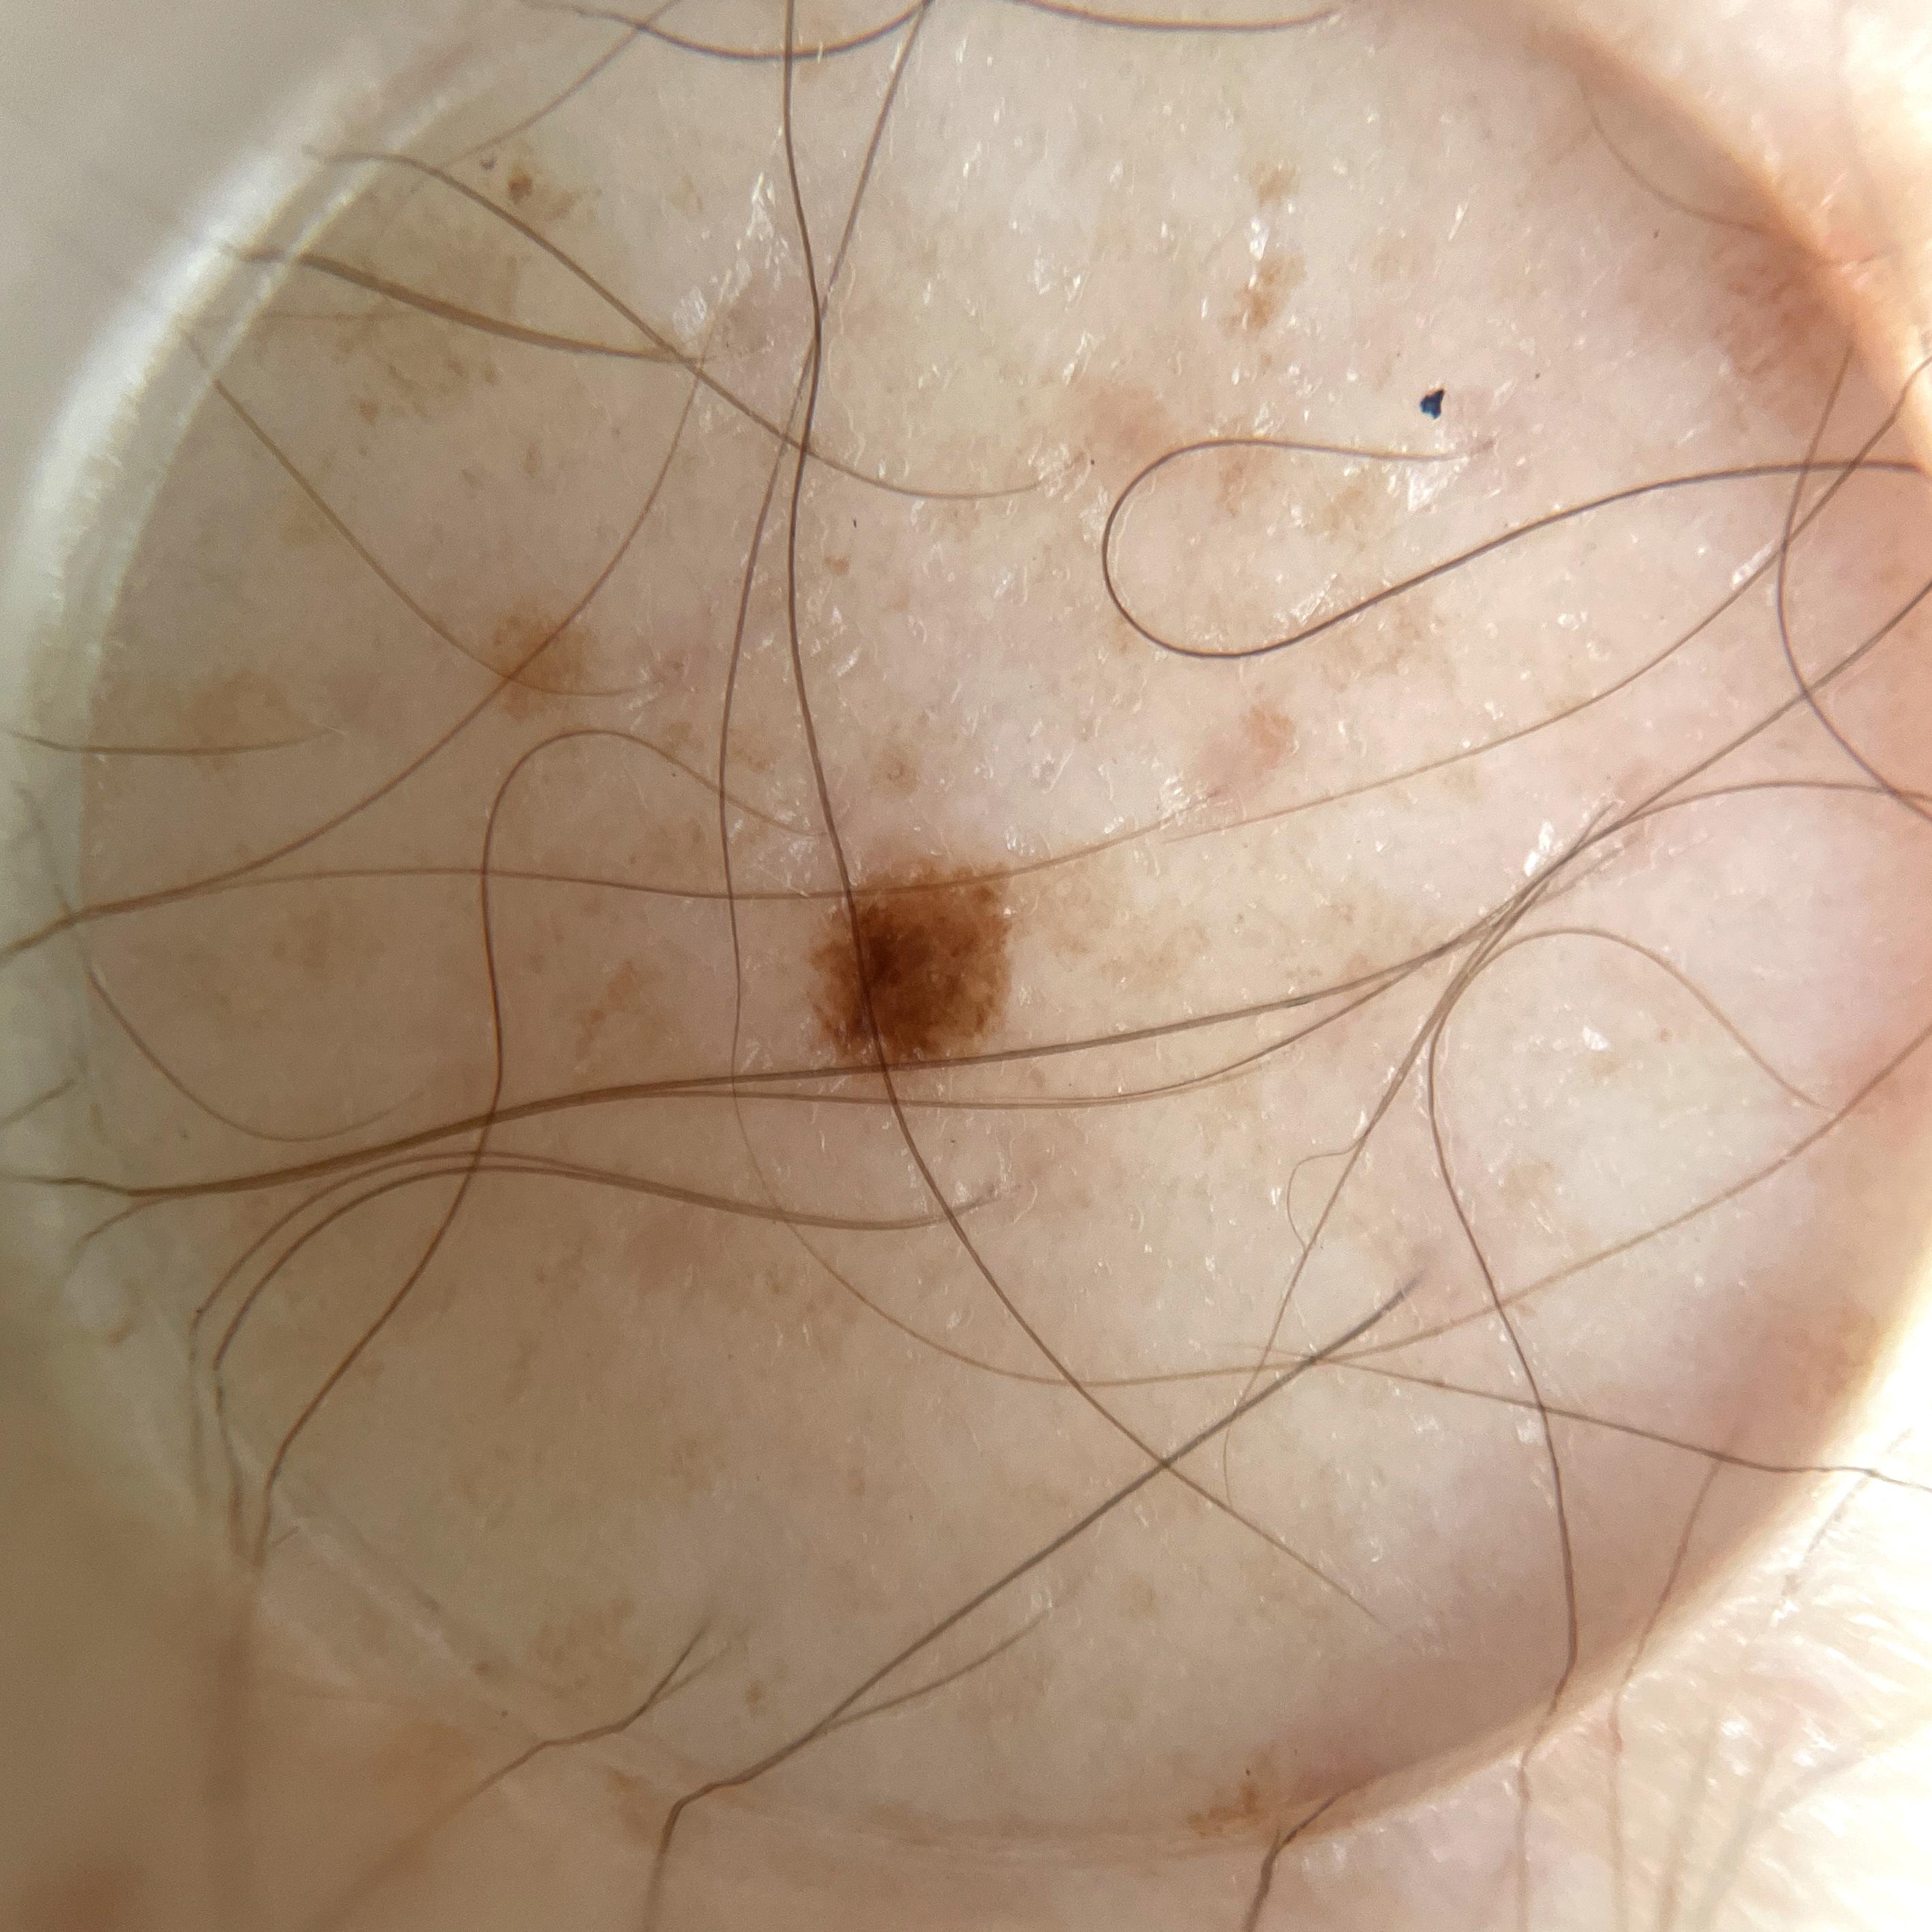

ISIC_5706752

Clinical

Field Value

acquisition_day 264

age_approx 55

anatom_site_1 Lower extremity

anatom_site_general lower extremity

concomitant_biopsy False

diagnosis_1 Benign

diagnosis_confirm_type single image expert consensus

family_hx_mm False

fitzpatrick_skin_type I

image_manipulation instrument only

image_type dermoscopic

lesion_id IL_0266048

patient_id IP_7932723

personal_hx_mm True

sex male